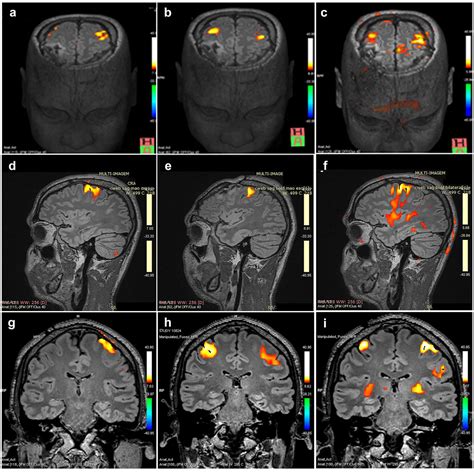

Diagnosing frontal lobe damage typically involves a multi-disciplinary approach. A neurologist or neuropsychologist will use a combination of imaging technologies and cognitive assessments to determine the extent of the damage. Magnetic Resonance Imaging (MRI) and Computed Tomography (CT) scans are the primary tools used to visualize physical damage, such as tumors, bleeding, or lesions.